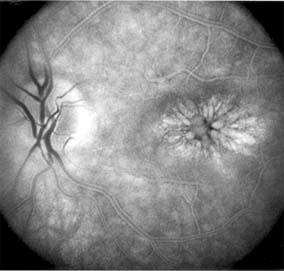

Figure 10-8

Figure 10-8: Typical macular lesion of acute multifocal posterior placoid pigment epitheliopathy.

AMPPPE typically affects healthy young patients who develop rapidly progressive bilateral vision loss in association with ophthalmoscopically visible multifocal flat gray-white subretinal lesions involving the pigment epithelium (Figure 10-8). The cause of this disease, which in many instances is associated with evidence of an influenza-like illness, is unknown; the course and nature of the illness suggests the possibility of viral infection. The characteristic feature of the disease is the rapid resolution of the fundus lesions and a delayed return of visual acuity to near-normal levels. Although the prognosis for visual recovery in this acute self-limited disease is good, many patients will identify small residual paracentral scotomas when carefully tested. Extensive pigmentary changes remaining during the late stages of AMPPPE may mimic widespread retinal degeneration; the clinical history and normal electrophysiologic findings aid in this differential diagnosis.